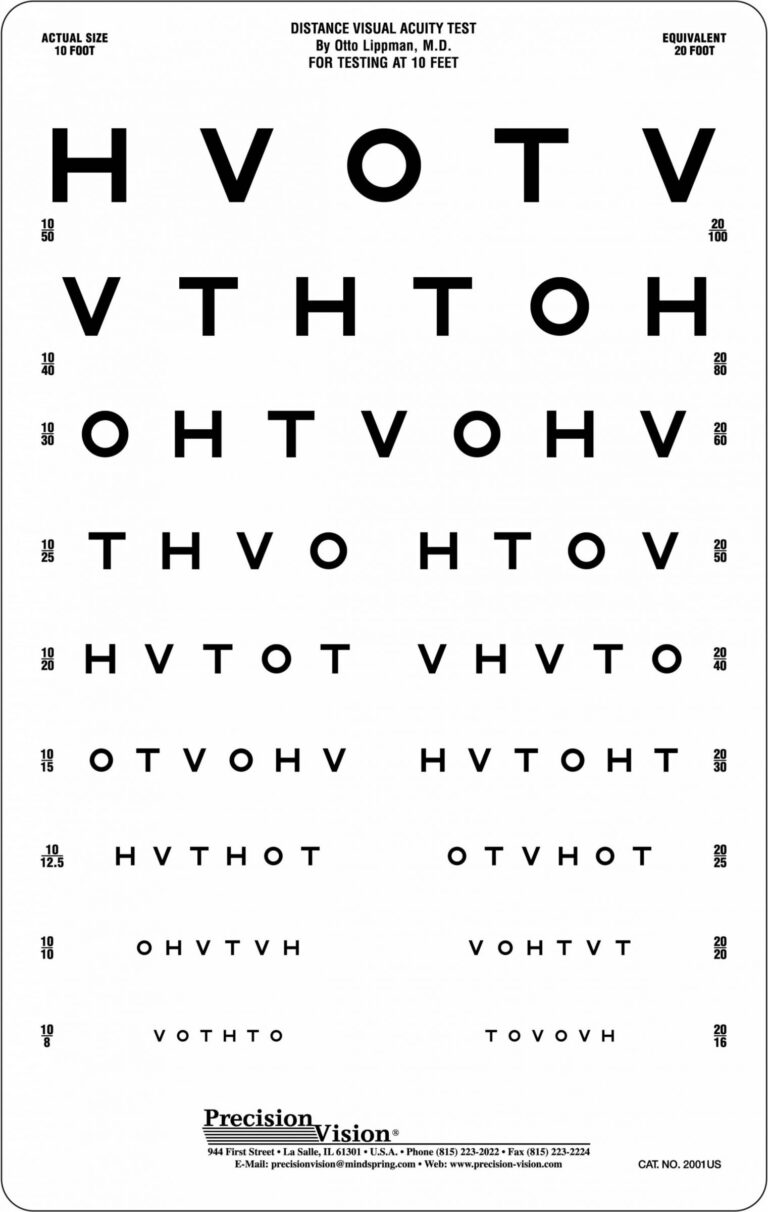

Hotv Eye Chart Printable

March 13, 2025

Have you ever needed an eye chart for testing your vision at home? Look no further! Our Hotv Eye Chart...

Read more